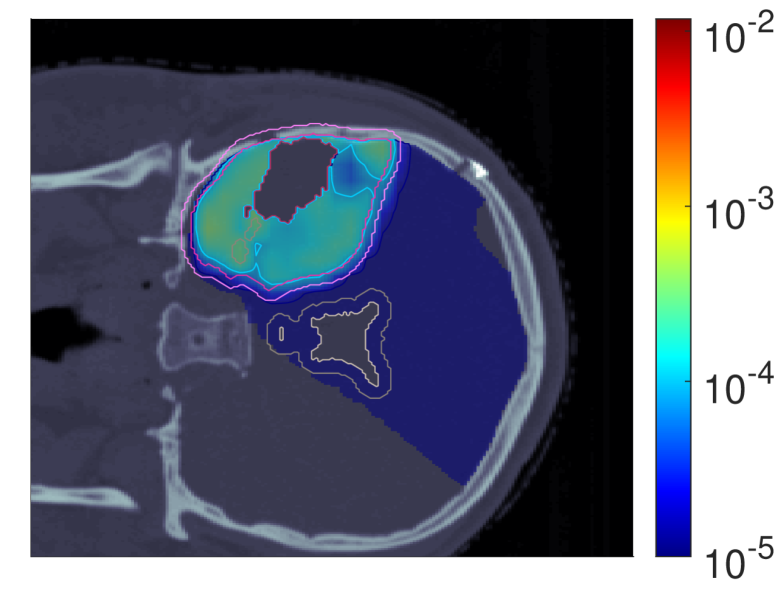

III.A.3 Probability of lesion origin pp

Figure 7 shows the POLO maps resulting from voxel-wise evaluation of the sigmoid-transformed linear predictor η\eta from Equation 1 with the input slice images for dRBE,fxd_{RBE,fx} and ldl_{d}.

NTCP30 %NTCP\approx{$30\text{\,}\mathrm{\char 37\relax}$} NTCP20 %NTCP\approx{$20\text{\,}\mathrm{\char 37\relax}$} NTCP10 %NTCP\approx{$10\text{\,}\mathrm{\char 37\relax}$}

pp (NTCPp)(NTCP_{p})

Refer to caption Refer to caption Refer to caption

pp (LSEp~)(LSE_{\tilde{p}})

pp (H~p)(\tilde{H}_{p})

pp (H~p~)(\tilde{H}_{\tilde{p}})

Figure 7: Optimal slice images of the probability of lesion origin pp for NTCPpNTCP_{p}, LSEp~LSE_{\tilde{p}}, H~p\tilde{H}_{p} and H~p~\tilde{H}_{\tilde{p}} at different NTCP levels. Considering the slice images for dRBE,fxd_{RBE,fx} and ldl_{d} from Figure 3 and Figure 5, the calculated pp values can be deduced from the prediction model. For example, hot spots are primarily found where high dRBE,fxd_{RBE,fx} values meet high ldl_{d} values, and for the voxels inside the 4 mm4\text{\,}\mathrm{mm} ventricular fringe where bb boosts the probability prediction. We take from these results that the POLO model-based optimization of the LGG sample patient’s proton plan achieves its goal, i.e., reducing pp in the region of interest.

For NTCPpNTCP_{p} and H~p\tilde{H}_{p}, we observed a (slight) reduction of dRBE,fxd_{RBE,fx} in the target volume and in the lower region overlapping with the VS, as well as a redistribution of ldl_{d} from the target volume to the margin of the PTV. Correspondingly, we see an overall reduction of pp in the target volume, together with an increasing attenuation of the hot spots around the marginal region of the PTV, and an elimination at the lower end of the VS. At strong down-regulation of the NTCP, the values are approximately one order of magnitude smaller, with peaks in the intersections to the 4 mm4\text{\,}\mathrm{mm} ventricular fringe and in regions where dRBE,fxd_{RBE,fx} and ldl_{d} intensify.

LSEp~LSE_{\tilde{p}} showed a decay of dRBE,fxd_{RBE,fx} inside but not outside the target volume, and almost constant values of ldl_{d}, and we recognize this pattern again in the pp distributions: hot spots are softened by the isolation of high-dose and high-LET regions, and the pp values in the target volume follow the negative trend for dRBE,fxd_{RBE,fx} at lower NTCP levels. Even the “dose gap” that occurs at an NTCP of 20 %20\text{\,}\mathrm{\char 37\relax} in the upper part of the target volume can be read from pp. Last, for H~p~\tilde{H}_{\tilde{p}} we can correlate the results for dRBE,fxd_{RBE,fx} and ldl_{d} again to understand pp. The higher ldl_{d} along the PTV margin is reflected by larger pp values and local hot spots, while the region around the GTV exhibits smaller pp values due to the reduction of dRBE,fxd_{RBE,fx}. At the lowest NTCP level, dRBE,fxd_{RBE,fx} contracts around the GTV, leaving only a slightly upward region at the left margin of the PTV which resembles the high-LET region, and hot spots where dRBE,fxd_{RBE,fx}, ldl_{d} and bb interact reinforcingly.

Globally, we observe an analogous shift in the “mass” of the pp distribution to lower values from the histograms in Figure 8. This indicates that the overarching goal of reducing pp during optimization can be fulfilled.